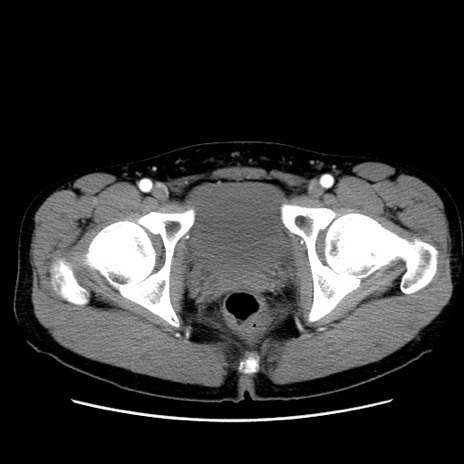

症例36(横断像)

【症例】20歳代 男性

【主訴】心窩部痛

【現病歴】今朝より上腹部痛あり。一旦軽快していたが再度出現したため救急要請。昨日夕に白身の魚を含む刺身を食べた。

【身体所見】BP 136/89mmHg、HR 74/min、BT 37.0℃、腹部:膨満、軟、心窩部に圧痛あり。反跳痛なし、筋性防御なし、腸雑音やや亢進あり。

【データ】WBC 17700、CRP 0.48